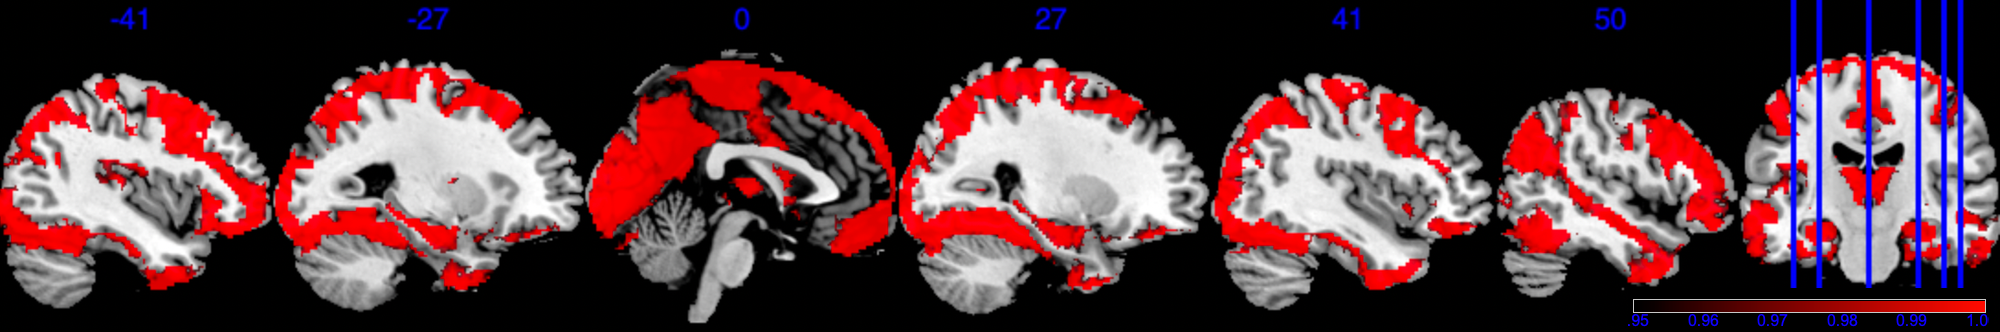

To define the analysis mask, we recall the definition of observed proportion (OP) at location to be , where is the set of all observed locations for individual . We define the group analysis mask as , i.e., the area where each voxel has at least 50% observed data. As shown in Figure 2, the group analysis mask with completely observed data (purple area) covers significantly less area compared to , which has at least 0.5 observed proportion (blue area). In the complete observed data, large portions of the brain regions are missing, notably including the orbitofrontal cortex, the inferior temporal cortex, and the amygdala—regions crucial for emotion processing. In particular, the mask with complete observed data contains only 52 out of the 110 regions in the Harvard-Oxford atlas.

After applying a common mask with an observed proportion of 0.5, we end up with that contains voxels. The image outcomes are standardized across subjects, i.e. where is the original image for subject location , is the sample mean, and SD[M(s)] is the standard deviation of . For each region, we apply the Matérn kernel function but with different and parameters (6), to account for the different smoothness of each region. Both and are determined through grid search so that the empirical covariance of and the estimated covariance by the Matérn kernel have the smallest difference in Frobenius norm. The number of bases is chosen so that the cumulative summation accounts for 90% of the total summation of all eigenvalues, hence we have a total number of . In Section 4.4.1, we provide a sensitivity analysis when the cutoff is based on 92% of the total summation.

For a visual representation, Figure 3(a) shows the voxel level PIP in the sagittal plane. The highlighted red regions represent voxels with greater than 0.95 PIP. Figure 3(b) presents the effect size of , with the highlighted area in the range . Note that from Figure 3(b), voxels with PIP greater than 0.95 also correspond to voxels with a larger absolute value of effect size. We notice that the activation region (defined by voxel level PIP greater than 0.95) has a negative effect . This can also be validated by the scatter plot in Section D in the Supplementary Material, where the image intensity generally has a negative association with age across all individuals.

Based on our results, we have the following general interpretations: (i) when controlling for the confounders, age has a negative impact on the neural activity for emotion-related tasks; (ii) the negative effect reflected from each voxel is of very small scale, shown as in Figure 3(b), indicating a very low voxel level signal-to-noise ratio; (iii) the top 5 brain regions with the highest RLAR are (a) right intracalcarine cortex, right supracalcarine cortex, and left Temporal fusiform cortex, anterior division, all considered as critical areas for high-level visual processing including face recognition; (b) left temporal fusiform cortex, anterior division, a key structure for face perception, object recognition, and language processing (Weiner and Zilles, 2016); and (c) right inferior temporal gyrus, anterior division, an area for language and semantic memory processing, visual perception, and multimodal sensory integration (Onitsuka et al., 2004). These top 5 regions are also consistently identified in the sensitivity analysis when using half of the data as training data, see Section 4.4.1.